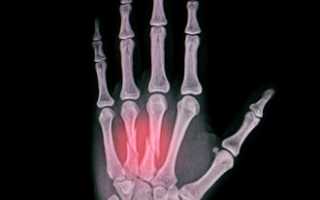

Окончательный диагноз перелома пястной кости со смещением ставится только после рентгенологического исследования, которое проводится в двух проекциях. При множественном переломе нескольких пястных костей может потребоваться дополнительное обследование с использованием компьютерной томографии.